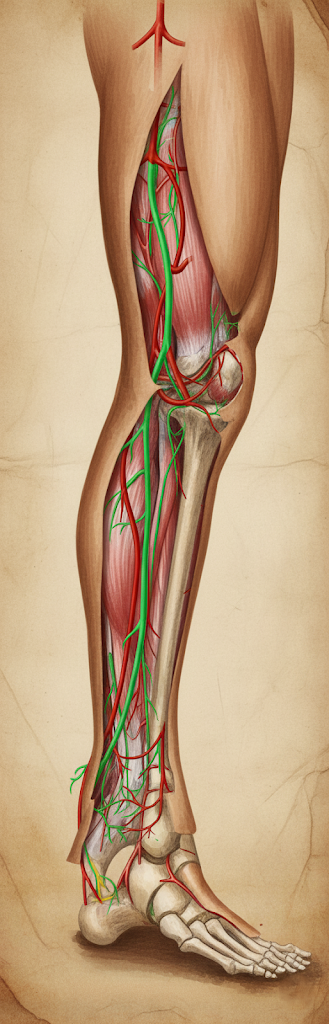

Arteria tibialis posterior, popliteal arterin (a. poplitea) diz arkasında iki ana terminal kolundan birini oluşturan, bacağın derin arka bölmesini ve ayak tabanını besleyen ana atardamardır. Türkçede “kaval kemiği arkası atardamarı” şeklinde karşılanır; Latin terminolojide a. tibialis posterior, İngilizcede posterior tibial artery olarak adlandırılır. Klinik dilde kısaltması ATP veya PTA şeklinde görülebilir.

Topografik anatomi ve komşuluklar

Köken: Arter, popliteal arterin distalinde, m. popliteus’un alt kenarı hizasında, kısa tibioperoneal trunk’tan çıkar (klasik anlatımda popliteal arterin “büyük terminal kolu” olarak da geçer).

Seyir:

- Başlangıçta arka (derin) kompartıman içinde, m. soleus’un arkus tendinözü altından geçer; kompartımanda m. tibialis posterior ve m. flexor digitorum longus ile yakın ilişki gösterir.

- Proksimal üçüncüde tibial sinir (n. tibialis) ile komşuluğu vardır; sinir genellikle arterin daha lateralinde başlayıp distal kesimlerde mediyaline geçebilir.

- Distalde medial malleolun arkasından, retinaculum musculorum flexorum altından—bilinen adıyla tarsal tünel—içinden geçerek ayak tabanına ulaşır.

Tarsal tünelde yapısal dizilim (anteriordan posteriyora):

Tibialis posterior tendonu (T), Flexor digitorum longus tendonu (D), Posterior tibial arter (A), Eşlikçi venler (V), Tibial sinir (N), Flexor hallucis longus tendonu (H).

Klinikte bu sıra “Tom, Dick And Very Nervous Harry” mnemonikle hatırlanır.

Duyusal–motor eşlik: Arter boyunca vena comitantes (eşlikçi derin venler) bulunur; n. tibialis arterle nörovasküler demet yapar.

Dallanma ve sonlanma

Proksimal dallar:

- A. fibularis (peronea): Çoğu kaynakta tibioperoneal trunk’tan ayrılsa da fonksiyonel olarak PT ile “aynı gövdeden” çıkar; lateral taraftaki derin arka kompartımanı ve fibulayı besler.

- Ramus circumflexus fibularis (değişken): Bazı bireylerde diz çevresi anastomozlarına katılır.

- Arteria nutricia tibiae: Tibianın en büyük besleyici arterlerinden biri olup kortikal–medüller dolaşıma katkı verir.

- Kas dalları: Derin arka kompartıman kaslarını (m. tibialis posterior, m. flexor digitorum longus, kısmen m. soleus) besler.

Ayak bileği düzeyi dalları:

- Rr. malleolares mediales ve rr. calcanei: Medial malleol çevresi ve kalkaneusa ince dallar.

Terminal dallar (ayak tabanı):

- A. plantaris medialis ve a. plantaris lateralis.

Lateral plantar arter, ayak tabanının derininde laterale yönelir, beşinci metatars boynuna doğru kıvrılır ve karşıdan gelen a. dorsalis pedis’in derin plantar dalıyla birleşerek arcus plantaris profundus’u oluşturur. Bu ark, aa. metatarsales plantares ve aa. digitales plantares aracılığıyla parmaklara son dalları gönderir. Medial plantar arter daha çok mediyal taban dokularını ve başparmak tarafını besler.

Anastomozlar: Ayak bileği ve ayak düzeyinde, anterior ve posterior kompartımanlar arasındaki zengin anastomotik ağ (arteriol düzeyinde kapiller yataklar ve arklar) ısının korunması, doku perfüzyonunun sürekliliği ve tıkayıcı hastalıklarda kollateral akım için kritiktir.

Vasküler dağılım (perfüzyon alanı)

- Bacak: Derin arka kompartıman kasları ve tibianın besleyici dalları.

- Ayak: Tarsal tünel distalinden itibaren tüm plantar (taban) dokuların ana arteriyel kaynağı; plantar ark aracılığıyla metatars başları ve dijital arterler.

- Klinik korelat: Bu nedenle posterior tibial arter, kritik ekstremite iskemisi ve diyabetik ayak değerlendirmesinde hedef damar niteliği taşır.